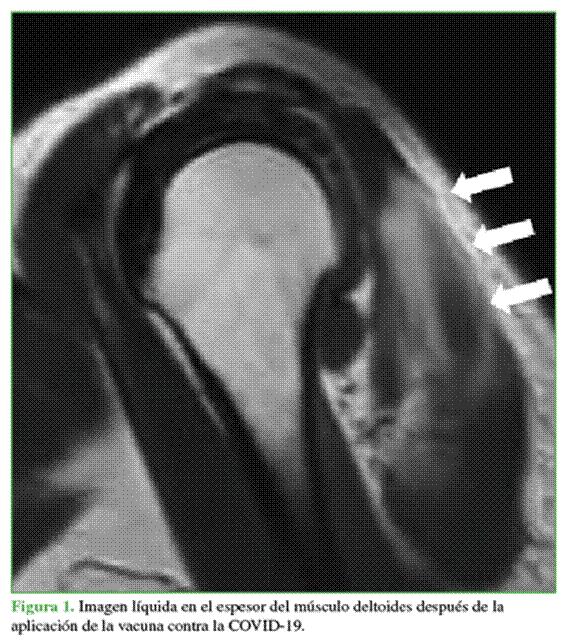

Se han reportado tendinopatía bicipital,4 sinovitis y derrame glenohumeral,14-16 cuadros de capsulitis adhesiva,5,8,11,16 miositis,16 formación de abscesos estériles intramusculares,15 osteítis,16 acumulación de líquido en el deltoides16 (Figura 1) y en el manguito rotador,16 artritis erosiva,16 artritis séptica,8 osteomielitis17 y osteonecrosis18.

Los hallazgos iniciales denotan cambios inflamatorios en partes blandas. Es frecuente detectar un aumento del líquido dentro de la bursa subacromial/subdeltoidea en la ecografía y la resonancia magnética (Figura 2). Salmon y cols.22 compararon estas imágenes iniciales con las diferidas a los cinco meses y observaron una regresión del derrame articular y una disminución de la bursitis, por lo que estos estudios pueden no ser muy demostrativos en cuadros crónicos.14

La miositis relacionada con la vacuna se manifiesta como un edema focal o difuso dentro del músculo en el lugar de la inyección, más comúnmente en el deltoides.16